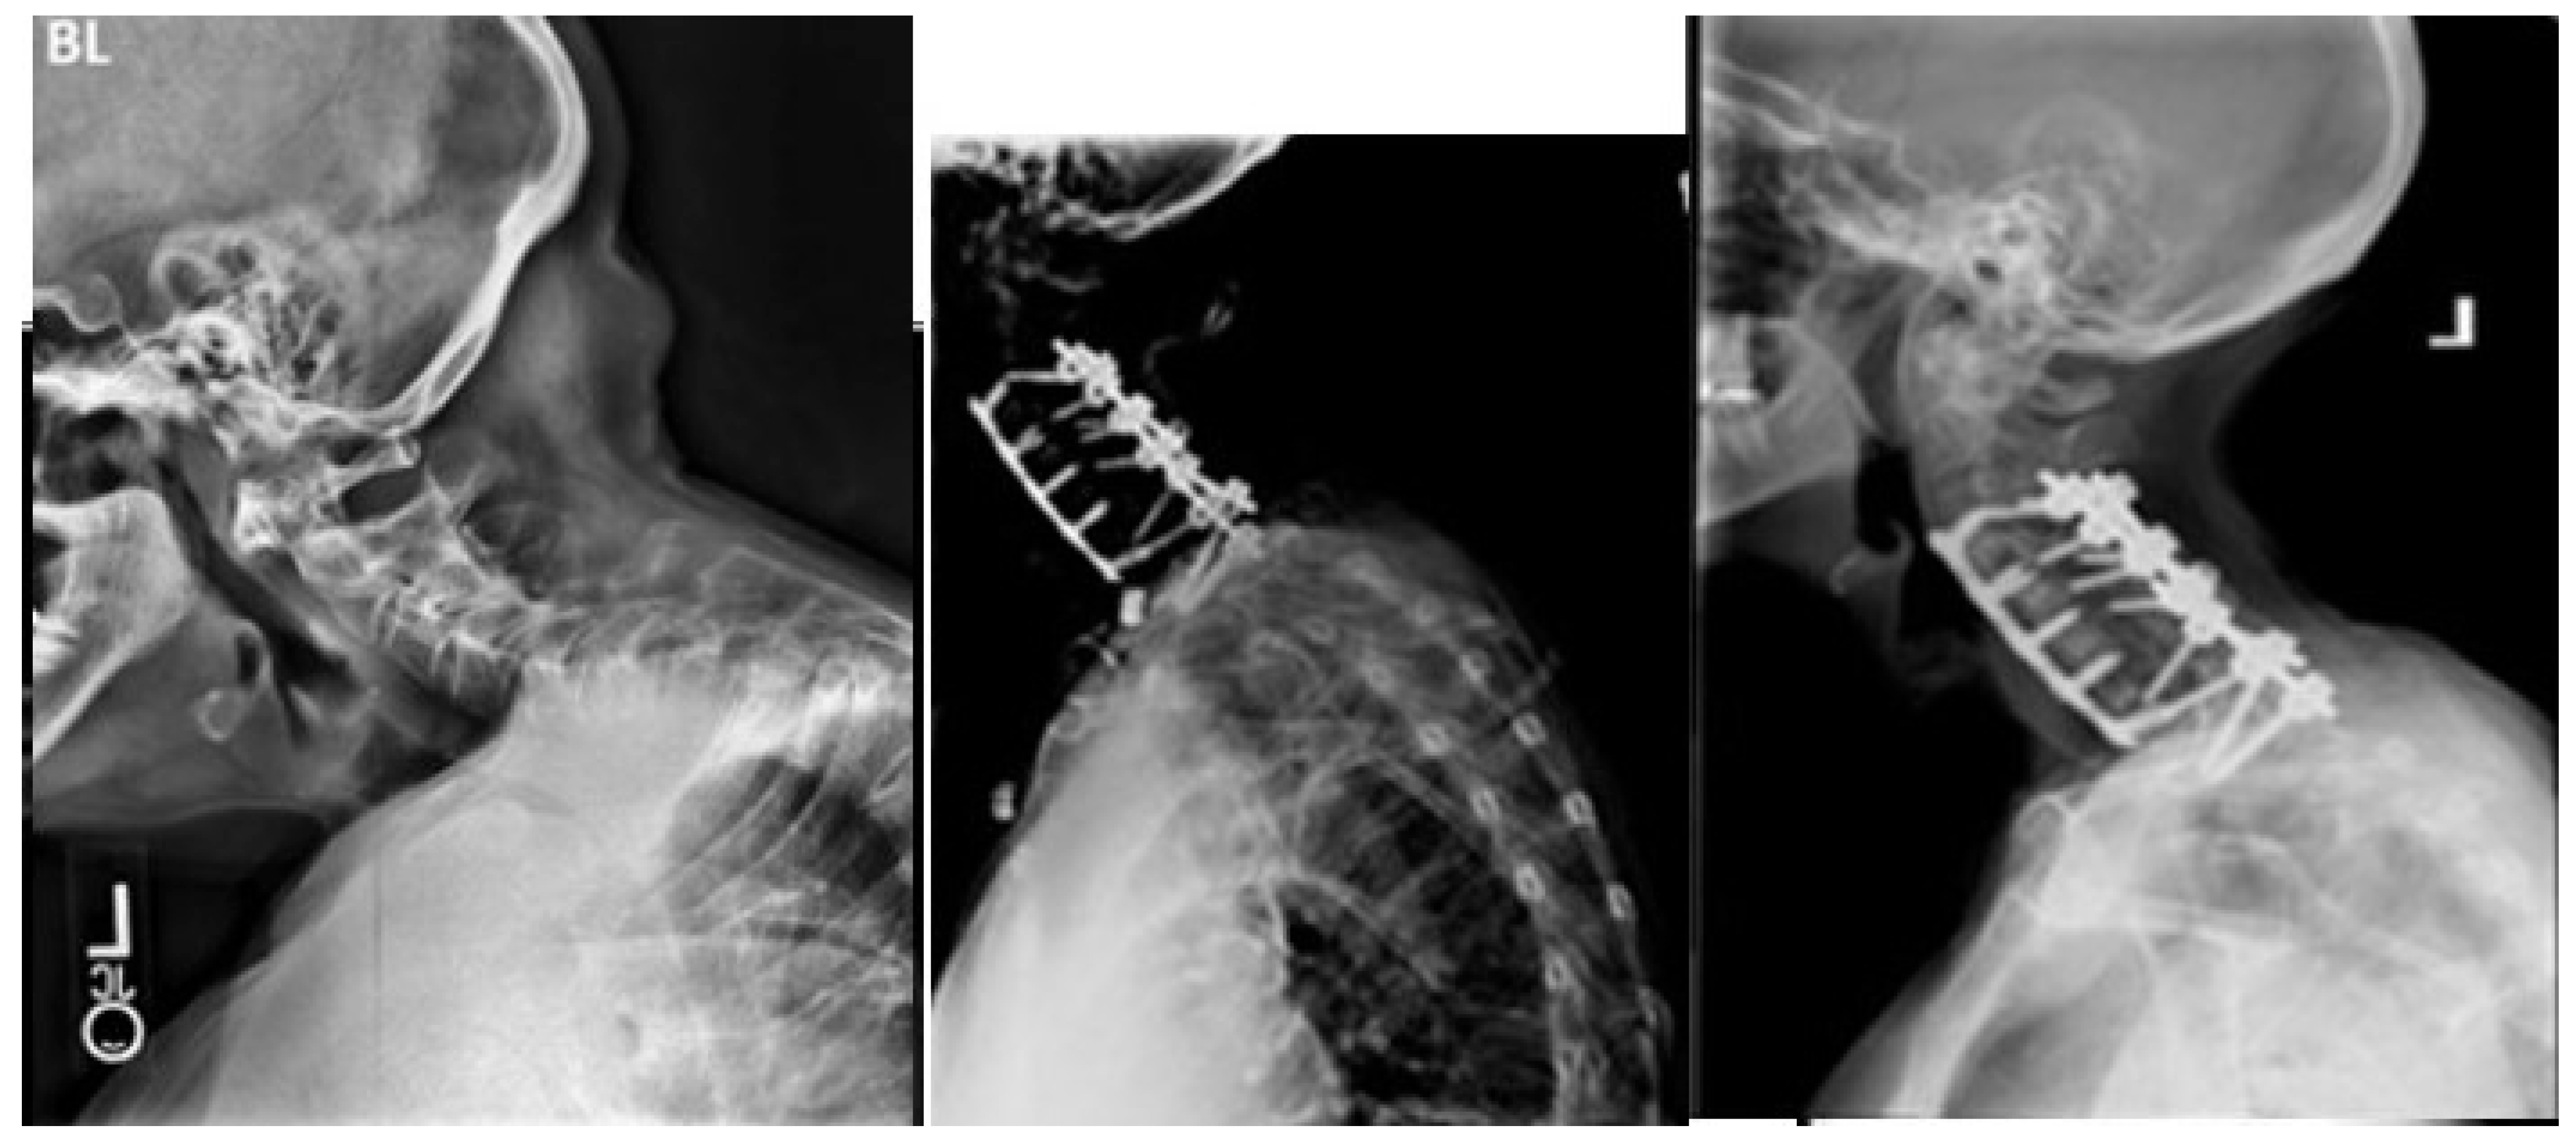

Figure 2.

A 71-year-old female from the DJK group. Images from left-to-right: preoperative, immediate postoperative, and 3-month postoperative X-rays. History of progressive right-sided neck pain with progressive radiculopathy and myelopathy. Symptoms unresolved with conservative measures. Underwent C3–C7 ACDF with C3-T1 posterior fusion. Symptoms initially showed some improvement up to 6 weeks, before showing gradual worsening.